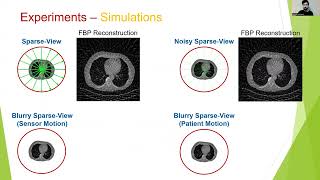

Tomographic Image Reconstruction: Introduction (Part 1) [L28] 3D Probabilistic Segmentation and Volumetry from 2D projection images

3D Probabilistic Segmentation and Volumetry from 2D projection images Beyond Local Processing: Adapting CNNs for CT Reconstruction

Tomographic Image Reconstruction: Introduction (Part 1) [L28] 3D Probabilistic Segmentation and Volumetry from 2D projection images

3D Probabilistic Segmentation and Volumetry from 2D projection images Beyond Local Processing: Adapting CNNs for CT Reconstruction